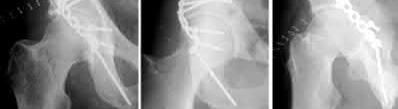

A 13-year-old boy with a BMI of 32 presents with right knee pain and an antalgic limp. Examination reveals obligatory external rotation with hip flexion. He is diagnosed with a slipped capital femoral epiphysis (SCFE). Which of the following is considered an indication for prophylactic pinning of the contralateral asymptomatic hip?

Options:

Correct Answer: Presence of an underlying endocrine disorder (e.g., hypothyroidism)

Explanation:

Prophylactic pinning of the contralateral hip in SCFE is controversial but is generally indicated in patients with underlying endocrine disorders (e.g., hypothyroidism, renal osteodystrophy, growth hormone deficiency), previous pelvic radiation, or highly skeletal immature patients (e.g., chronological age < 10 for boys, modified Oxford bone age < 16). These populations have a very high risk of bilateral involvement. Age > 15, male sex, and slip severity alone are not strict indications for prophylactic pinning.